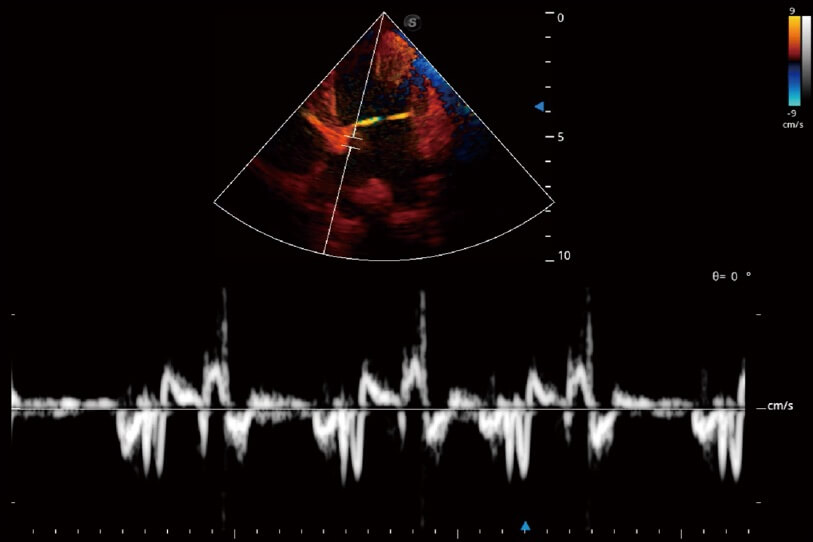

實(shí)時(shí)用顏色表示心肌組織運(yùn)動(dòng),觀察和定量組織的運(yùn)動(dòng)情況,對(duì)快速檢測(cè)與評(píng)估心肌的灌注和活性、電傳導(dǎo)及心肌收縮和舒張功能等均能提供重要的診斷信息。

通過(guò)創(chuàng)新的 Matrix E自適應(yīng)濾波器和超長(zhǎng)時(shí)間域算法,極大提升超低速微細(xì)血流的檢出能力,同時(shí)更精準(zhǔn)地濾除軟組織和噪聲信號(hào),為獸用醫(yī)生提供以往無(wú)法通過(guò)常規(guī)血流獲得的疾病診斷信息。